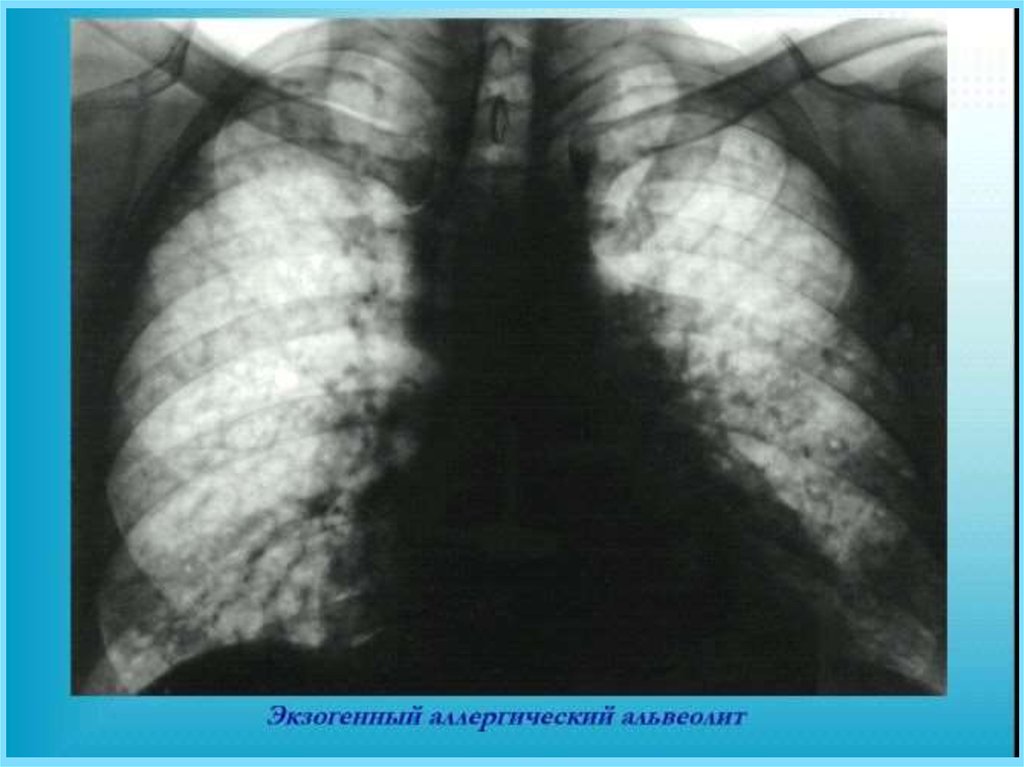

Экзогенный аллергический альвеолит